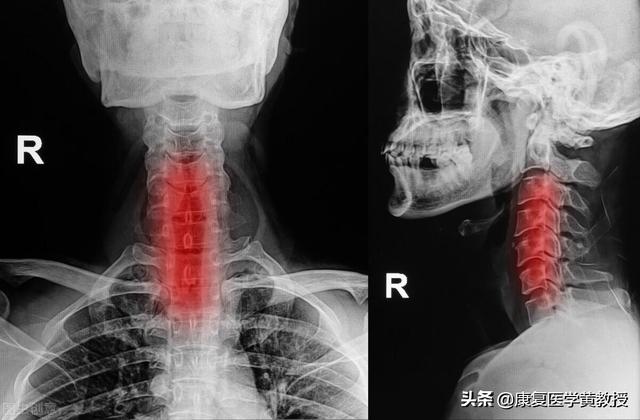

1) Tout d'abord, vous devez vous rendre à l'hôpital.Le diagnostic de spondylose cervicale peut être confirmé par des examens d'imagerie conventionnels tels que les radiographies, le scanner et l'IRM.et la gravité de l'affection ;

Avec la popularité des ordinateurs et des téléphones portables, jeunes et vieux, hommes et femmes, tout le monde est devenu "tête basse", maintient longtemps une posture, fatigue chronique, de sorte que la spondylose cervicale n'est plus le "brevet" des personnes âgées, mais devient progressivement une norme pour les jeunes. Qu'est-ce que la spondylose cervicale ?La spondylose cervicale est un terme général désignant l'arthrose de la colonne cervicale, la spondylite cervicale hyperplasique, le syndrome des racines nerveuses cervicales et le prolapsus du disque cervical.La colonne cervicale est une zone structurellement complexe et la spondylose cervicale est une maladie aux causes multiples et aux manifestations diverses.

Il s'agit d'une irritation ou d'une compression des tissus adjacents de la colonne vertébrale, des nerfs, des vaisseaux sanguins et de l'œsophage, due à la dégénérescence du disque cervical et à ses modifications secondaires, et qui provoque les symptômes et les signes correspondants.

catégorisation

La spondylose peut être classée en spondylose des racines nerveuses, spondylose de la moelle épinière, spondylose de l'artère vertébrale cervicale et spondylose sympathique en fonction du site de compression et des manifestations cliniques.